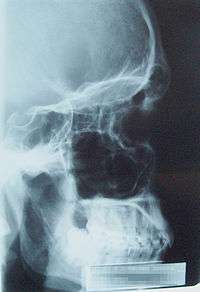

Lateral projection of the paranasal sinuses | |

Paranasal sinuses are a group of four paired air-filled spaces that surround the nasal cavity.[1] The maxillary sinuses are located under the eyes; the frontal sinuses are above the eyes; the ethmoidal sinuses are between the eyes and the sphenoidal sinuses are behind the eyes. The sinuses are named for the facial bones in which they are located.

Humans possess four paired paranasal sinuses, divided into subgroups that are named according to the bones within which the sinuses lie:

- The maxillary sinuses, the largest of the paranasal sinuses, are under the eyes, in the maxillary bones (open in the back of the semilunar hiatus of the nose). It is innervated by the trigeminal nerve.[2]

- The frontal sinuses, superior to the eyes, in the frontal bone, which forms the hard part of the forehead. It is also innervated by the trigeminal nerve.[2]

- The ethmoidal sinuses, which are formed from several discrete air cells within the ethmoid bone between the nose and the eyes. They are innervated by the ethmoidal nerves, which branch from the facial nerve.[2]

- The sphenoidal sinuses, in the sphenoid bone. It is innervated by the trigeminal nerve.[2]